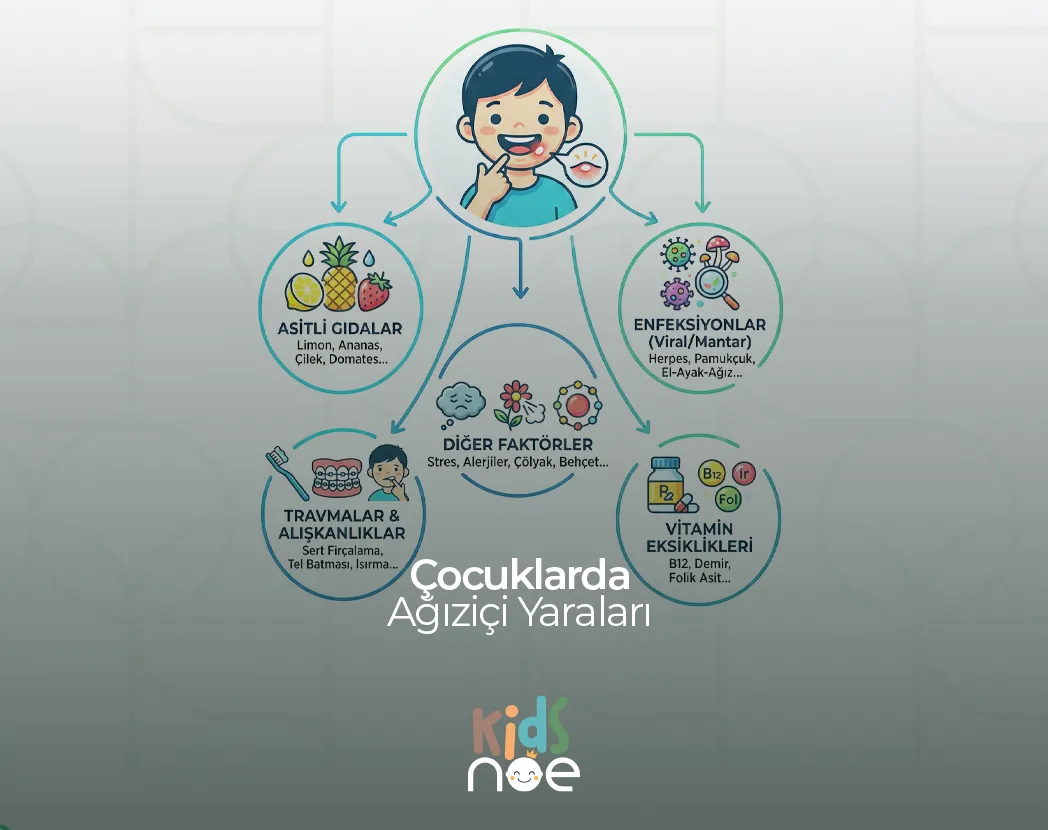

Çocuklarda ağız içi yaraları; aft, travma, viral enfeksiyon veya vitamin eksikliğine bağlı gelişebilir. Belirtiler ve iyileşme süreci hakkında bilgi.